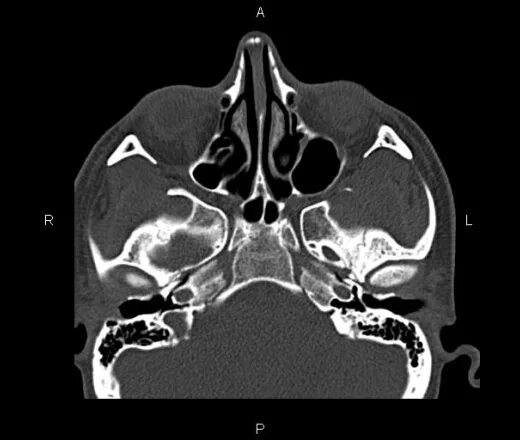

Кт онп что это